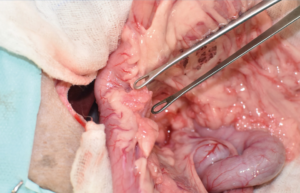

La cirugía de elección es la pancreatectomía parcial y la resección de losnódulos linfáticos (NNLL) centinelas (imágenes 3A-3I). La quimioterapia intracavitaria puede controlar la efusión por carcinomatosis secundaria, pero ofrece una respuesta paliativa de corta duración. La pancreatectomía completa o pancreaticoduodenectomía (técnica de Whipple), descritas en el perro, presentan altas tasas de morbilidad y mortalidad operatorias. La técnica de Billroth II es una opción paliativa a corto plazo en casos de obstrucción intestinal. En un estudio retrospectivo en 34 pacientes felinos con carcinoma pancreático exocrino primario la enfermedad se asoció con una historia previa de diabetes mellitus.35 El carcinoma pancreático exocrino canino se caracteriza por una alta tasa de metástasis y un pronóstico grave general.37

Imágenes 3A – 3I. Secuencia de imágenes quirúrgicas en un perro (con las imágenes del TC), durante una pancreatectomía parcial del lóbulo izquierdo y cuerpo del páncreas, usando un sellador vascular/tisular, por carcinoma pancreático.